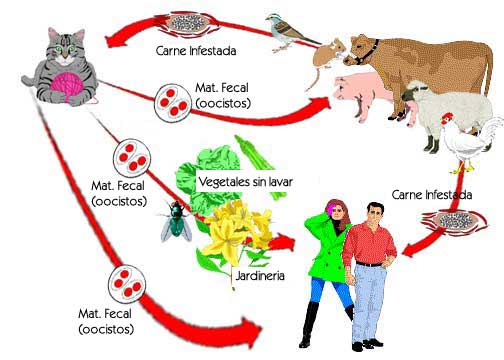

La toxoplasmosis es una enfermedad clínica causada por una infección extrema de toxoplasma gondii, un parásito capaz de infectar a todos los animales de sangre caliente, incluyendo los humanos. La toxoplasmosis es una enfermedad clínica causada por una infección extrema de toxoplasma gondii, un parásito capaz de infectar a todos los animales de sangre caliente, incluyendo los humanos.

Aunque las infecciones de toxoplasma son relativamente comunes, se estima que entre un 30 y un 50% de la población está infectada, rara vez se desarrollan en la enfermedad toxoplasmosis, sin embargo, conlleva serios riesgos para el futuro bebé si se contagia durante el embarazo.

La Toxoplasmosis es una enfermedad infecciosa ocasionada por un protozoo parásito llamado Toxoplasma gondii, que puede causar tanto infecciones leves y asintomáticas, así como infecciones mortales que afectan mayormente al feto, llamándose en este caso Toxoplasmosis congénita.